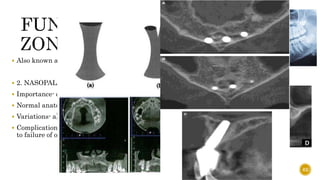

 Also knownas the “traumatic zone”  2. NASOPALATINE / INCISIVE CANAL  Importance- carries nasopalatine nerve and vessels  Normal anatomy  Variations- a) Angulation b) Number  Complication- if an implant contacts neural tissue in this canal, it could lead to failure of osseointegration or sensory dysfunction. 62

 3. NASALCAVITY  4. CANALIS SINUOSUS - is a bone canal in the maxilla that branches from the infraorbital canal and ends laterally to the anterior nasal spine and contains the anterior superior alveolar neurovascular bundles 63